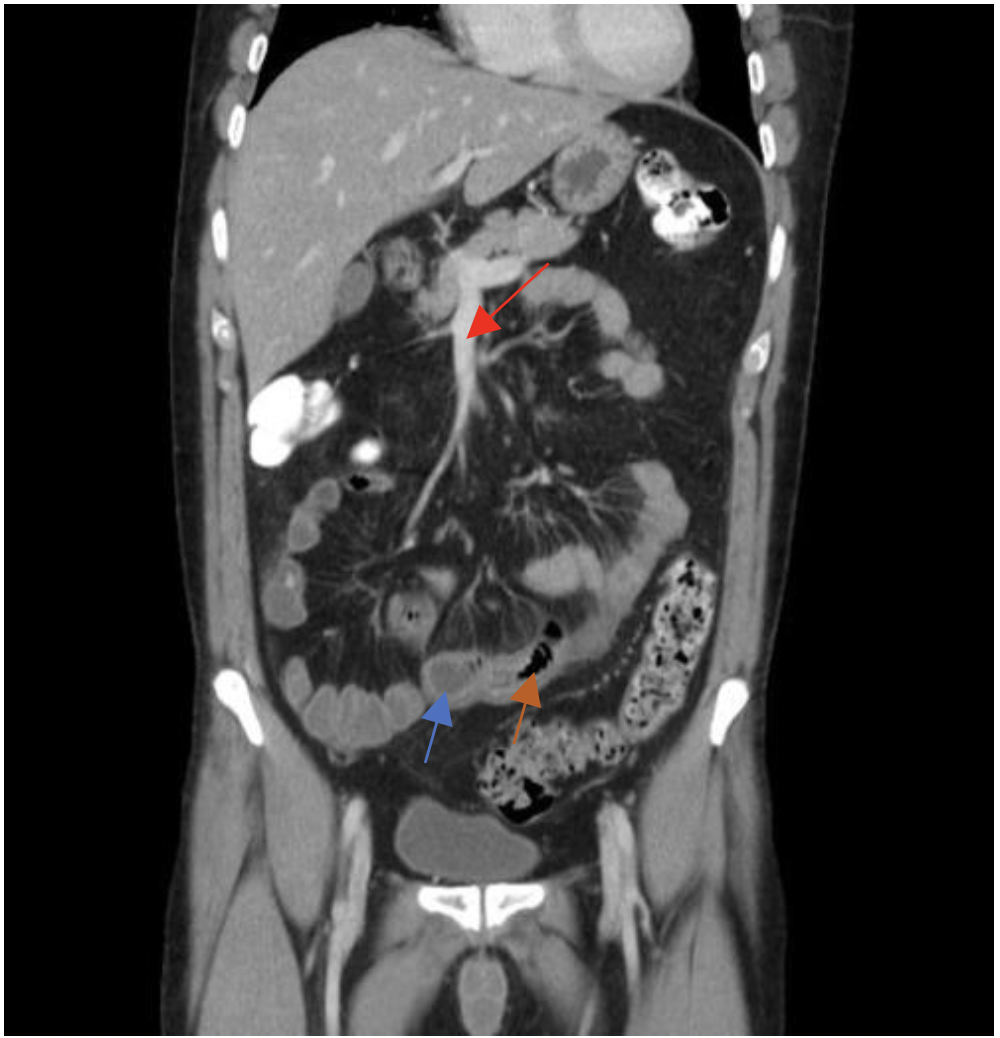

של חולה קרוהן MRI בתמונה

מה החצים מסמלים?

גדושים SMA חץ אדום- הענפים של ה

חץ כחול- דופן המעי עבה ומלאה מים

חץ כתום- כיבים

בנוסף ניתן לראות קשריות לימפה נפוחות שמעידות על דלקת (?)